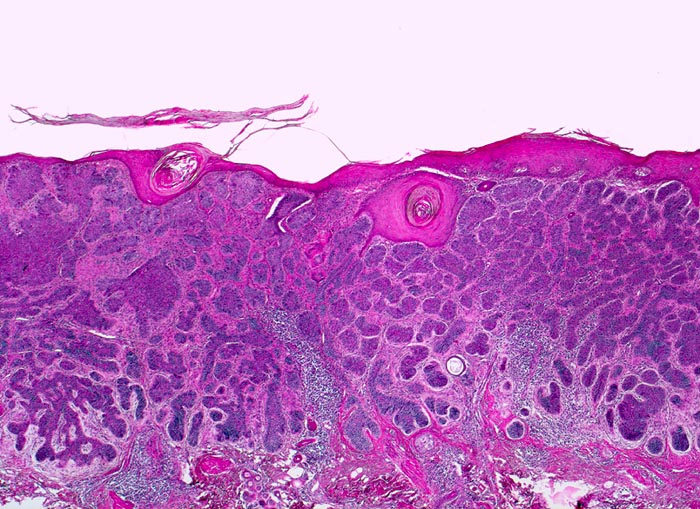

• Fokale oberflächliche Ulzeration bzw. Erosion der Epidermis über dem Tumor.

• Solide blaue Tumorzellplatten in der Dermis, teils mit Kontakt zur Epidermis.

• Im Zentrum einzelner Tumorzellplatten Verhornung, Tumornekrosen oder Hohlraumbildungen.

• Die Dermis in der tumorfreien Haut zeigt eine deutliche solare Elastose als Zeichen der chronischen UV Schädigung.